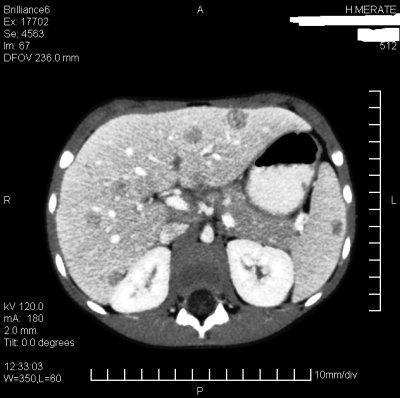

Un'ecografia addominale rilevava �a carico del fegato e della milza multiple lesioni focali solide, ipoecogene; almeno sei a livello della milza e a carico del fegato interessanti entrambi i lobi con dimensioni variabili da pochi mm a un massimo di un cm. Lesioni epatiche a contorni un po' pi� sfumati, quelle spleniche ben delimitabili dal parenchima circostante. Ascessi? Interessamento d'organo in malattia leucemoide-linfomatosa?�. A seguito di tale referto, veniva eseguita una TAC addominale (Figura 1) che confermava nel contesto del parenchima epatico e splenico la presenza di multiple lesioni focali ipodense di diametro compreso tra i 5 ed i 22 mm; reperto compatibile in prima ipotesi con ascessi multipli.

Figura 1. TAC addominale con mezzo di contrasto. Nel contesto del parenchima epatico e splenico si evidenziano multiple lesioni focali ipodense rotondeggianti di diametro compreso tra i 5 ed i 22 mm. Il reperto � pi� evidente a livello delle lesioni epatiche ed � compatibile in prima ipotesi con ascessi multipli.